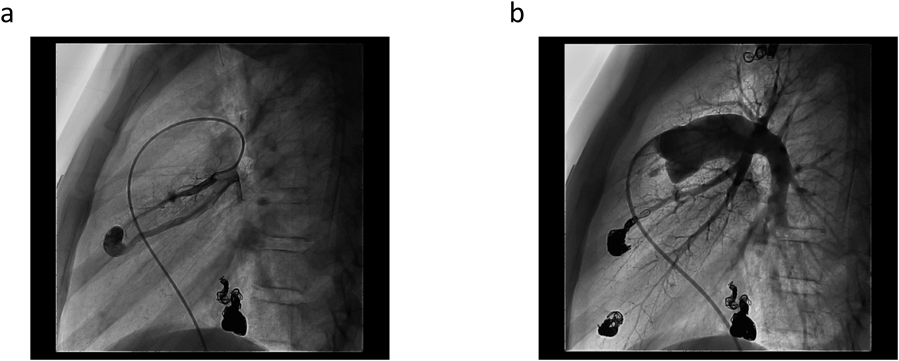

Pediatric Cardiology and Cardiac Surgery 33(3): 241-246 (2017)

Fig. 3 Coil embolization of a PAVM

Simple type PAVM at S5 of left lung. (a) before embolization. (b) after embolization. Angiogram shows good occlusion, without flow through the PAVM.

塞栓後SpO2 98%(room air)の改善が得られ,主だった残存PAVMの流入動脈径は1.5 mm未満であり,吻合部・瘻までのアクセスも困難と判断し終了とした.